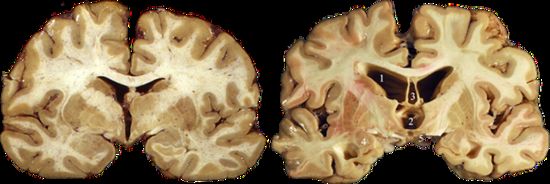

目前认为,慢性创伤性脑病是一种由反复撞击引起的、神经元退行性病变,且跟撞击频率、强度密切相关。临床上可出现学习、记忆、运动等功能受损,表现出易怒、抑郁、自伤倾向等行为特征。CTE患者的脑部在外观上可无异常,也可出现额叶萎缩、脑室扩张等表现。[10]在内部,CTE最典型的特征,是Tau蛋白异常聚集。[11]

左图为正常大脑,右图为CTE患者大脑